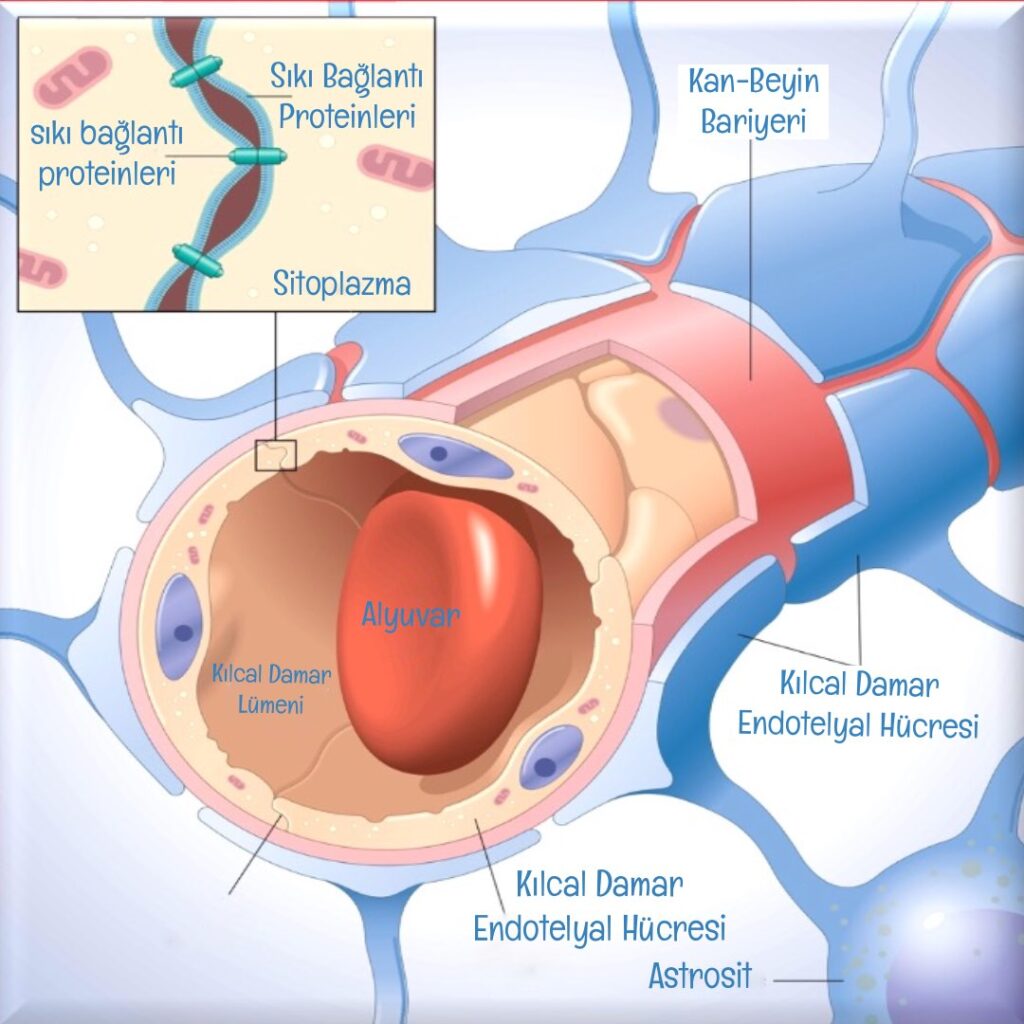

Bu mucize sistem resimde görüldüğü üzere şu yapılardan oluşur: [1]

- Kılcal damarların iç yüzeyini kaplayan endotel hücreleri

- Damar duvarının dış tabakasındaki perisit hücreleri,

- Beynin gri maddesinde bulunan yıldız şeklindeki astrositik hücreler,

- Beynin kan damarlarının iç yüzeyindeki epitel hücrelerinin tabanını kaplayan, onları alttaki bağ dokusundan ayıran ve ayrıca sinir hücrelerini örten bazal membran,

- Koroid pleksus: Beyni ve omuriliği çevreleyen beyin omurilik sıvısını üretir,

- Pisiform ve araknoid zarlar: beyni çevreleyen üç katmanlı zarın iç iki katmanını oluşturur.

KAN-BEYİN BARİYERİNİN YAPISI

Kan-beyin bariyeri, vücuttaki işlevine uygun olarak yaratılmış karmaşık hücresel yapılardan oluşur. Bariyer sayesinde maddelerin beyin hücrelerine geçişi fiziksel olarak güçlü bağlarla, metabolik olarak da enzimlerle kontrol edilir. Merkezi sinir sisteminin kılcal damarları, onları vücuttaki kılcal damarlardan ayıran birkaç özelliğe sahiptir. Bunlardan biri, beyin kılcal damarlarını kaplayan hücreler (endotel) arasındaki sıkı bağlantılar ve bu kılcal damarların üzerinde sürekli bir zarın (bazal membran) bulunmasıdır. Ancak ilginç bir şekilde, kan-beyin bariyerinin endotel hücreleri arasında yüksek elektrik direnci vardır. Diğer dokularda 3-33 W/cm2 olan direnç, kan-beyin bariyerinde 1500-2000 W/cm2’ye kadar yükselir. Bu elektrik alanı, sıvıların ve iyonların hücre içine ve dışına taşınmasına bir engel oluşturarak geçirgenliği azaltır. Ayrıca kan-beyin bariyerinde, vücuttaki diğer kılcal damarlarda olduğu gibi molekül ağırlığı 10.000’den (g/mol) az olan maddelerin geçebileceği delikler veya yarıklar bulunmaz. [3]